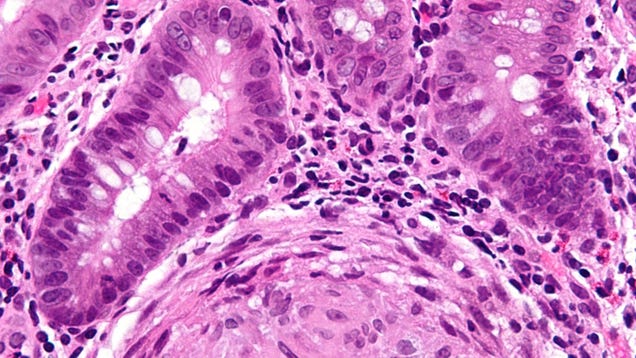

Researchers in the UK appear to have discovered a pivotal genetic cause of inflammatory bowel disease. In a new study Wednesday, the team found evidence of a specific genetic flaw that seems to play a key role in driving immune cells to attack the guts of those with IBD—a flaw found in nearly all the cases they…